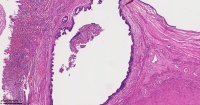

炎性息肉?潴留囊肿?腺体是否有问题?

性别

女

年龄

51岁

临床诊断

一般病史

宫颈赘生物

标本名称

大体所见

息肉。

稳妥起见最好做一做免疫组化。